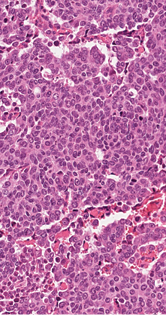

2 pav. Trys naviko komponentai: solidiniai epiteioidinių ląstelių lizdai, kuriems būdingos pavienės spindžius primenančios struktūros (A), pluoštais besidėstančios šeivinės ląstelės (B) ir diskohezyvios „rabdoidinės“ ląstelės, turinčios ekscentrišką citoplazmą (C)

Mikroskopiniuose preparatuose (1 pav.) matyti infiltratyviai žarnoje plintantis navikas, sudarytas iš trabekulinų, lizdinių ir solidinių struktūrų su pavieniais likutiniais spindžiais, kurias formuoja mišri ląstelių populiacija (2 pav.): dominuoja epitelioidinės kohezyvios ląstelės (apie 40 proc. naviko), pasižyminčios negausia ir vidutinio gausumo eozinofiliška citoplazma, smulkaus ir stambesnio kalibro centruotais, ovaliais arba nelygaus kontūro, polimorfiškais branduoliais. Šeivinės ląstelės sudaro apie 30 proc. naviko, ląstelių citoplazma vidutinio gausumo, eozinofiliška, ląstelėse ištęsti vidutinio kalibro branduoliai. Likusią dalį (apie 30 proc. naviko) sudaro diskohezyvios rabdoidinės išvaizdos ląstelės periferizuotais branduoliais ir ryškiomis nukleolėmis, ekscentriška citoplazma ir eozinofiliniais intracitoplazminiais inkliuzais. Matyti gausios mitozės (40/2 mm2), nekrozės iki 10 proc. naviko tūrio, granuliacinis audinys išopėjusiame paviršiuje. Identifikuotas perineurinis naviko plitimas ir intravaskulinė (smulkių šakų ir intraveninė) invazija; naviko struktūros siekė cirkuliarų rezekcijos kraštą. Antrąjį židinį formavo analogiškos to paties naviko struktūros su negausiu likutiniu limfoidiniu audiniu periferijoje (tikėtina metastazė pasaito limfmazgyje, ekstranodaliai plintanti į žarnos sieną).